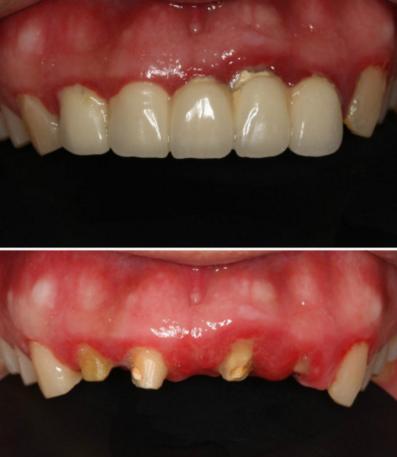

很多做过美容冠的患者在后期因为出现各种问题而拆除冠后,常常可以看到剩余的牙齿和牙周组织惨不忍睹,严重的甚至无法保留而只能拔除。

以下是做过“美容冠”患者的患者牙齿,触目惊心啊~

@西安牙医老聂:说中无所不能的“美容冠”!

@佳头2011:患者烤瓷修复四年,美容冠